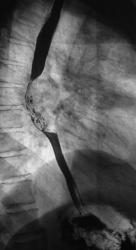

Линейные томограммы в боковой проекции

По представленным снимкам, у меня сложилось впечатление что пищевод как бы сдавлен извне (овал), возможно образованием в заднем средостении; при этом на довольно продолжительном участке есть нарушение архитектоники складок слизистой с множественными участками barium depletion (стрелки), свидетельствующими в пользу изъязвления.

Выводы: изначально хотелось бы узнать анамнез и жалобы; но так как их не представлены, буду рассуждать опираясь только на семиотику. У меня 2 варианта: опухоль пищевода с преимущественно интра-муральным ростом или образование средостения с прямой инвазией пищевода вплоть до слизистой оболочки, в данном случае может быть много вариантов. Моя рекомендация-конечно КТ, посмотреть стенки пищевода и окружающие структуры.

Исходя из вышесказанного, по данному случаю: сдавление просвета и смещение пищевода мягкотканным образованием, выходяшим за пределы стенки, изъязвление передней стенки пищевода. Заключение: подслизистая опухоль пищевода с изъязвлением, вероятнее всего лейомиома. Рекомендации: эндоУЗИ с биопсией, КТ.

После проведенного рентгенологического исследования органов грудной полости - рентгенографии и томографии, при которой были выявлены увеличенные лимфатические узлы в корнях лёгких и средостении, было проведено рентгенотелевидение пищевода с прицельной рентгенографией и исследованием пищевода на трохоскопе, с контрастированием пищевода водной взвесью сернокислого бария "различной консистенции" - от сверхжидкого - до пастообразного, для "выяснения состояния" заднего средостения. Была зарегистрирована и документирована "локальная деформация пищевода" на протяжении 9,5 см. с перестройкой структуры "рельфа слизистой оболочки".